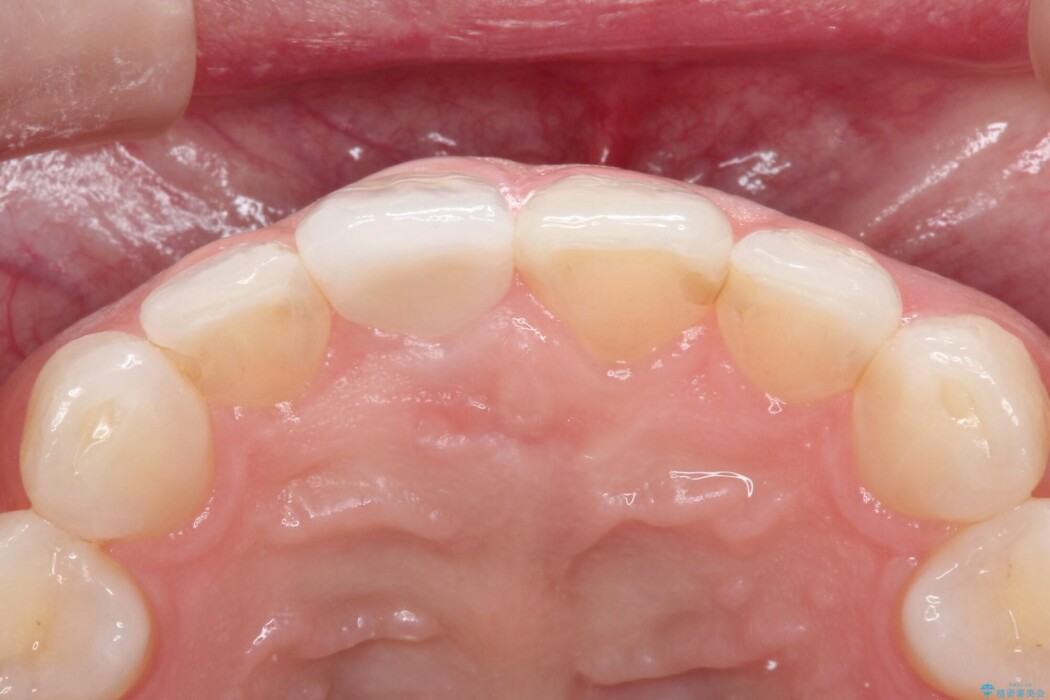

該当箇所は他院で10年ほど前に根管治療をされており、歯の根っこまで感染が進み炎症を起こす「根尖性歯周炎」の予防のためまず根管治療から行うこととしました。

根管治療後の被せものはオールセラミッククラウンを選択し、またホワイトニングもご希望でしたのでホームホワイトニングを合わせて行いました。

被せものは歯とかぶせ物の適合がとても重要です。適合が悪い被せものだと、外れやすい状態となったり、歯とかぶせ物の間に隙間が生じ汚れがたまることによって虫歯が生じる原因となります。

当院では適合が良く精度の高い被せものを追求するために、サージテルや型取りの材料にシリコン材を使用しております。